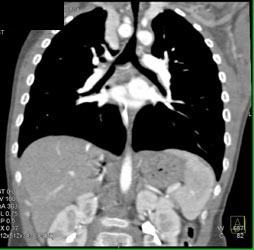

Airway Narrowing Due to Double Arch